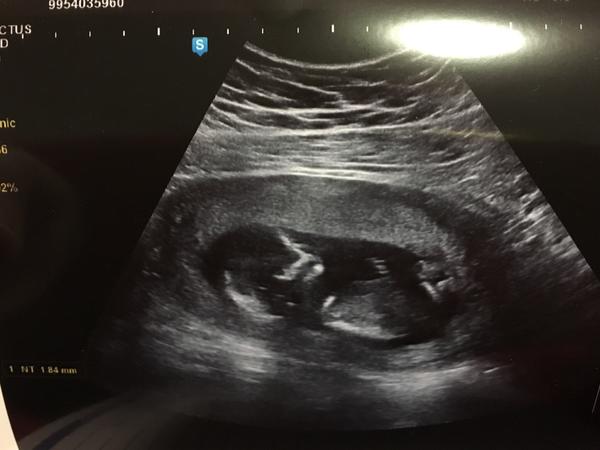

@sarlotaholubova kopiruju z netu "Šíjové projasnění – nuchální translucence NT. Ultrazvukové vyšetření dokáže odhalit vrozené vývojové vady již koncem prvního trimestru. Zde se jedná o měření množství volné tekutiny ( tloušťky kožní řasy, která takto vzniká ) v záhlaví plodu. Hodnota NT plodu se zvyšuje s temenokostrční délkou plodu – viz níže, a proto je nezbytné vzít v úvahu délku těhotenství pro posouzení, zda je zjištěná tloušťka NT zvýšená. Za hraniční se považují hodnoty kolem 2,5 mm. V případě výrazně zvýšené hodnoty NT ( nad 95. percentilem )je vyšší riziko postižení dítěte genetickým syndromem. Nejčastěji se hovoří o Downově syndromu ( nesprávně mongolismu ). Existuje však i riziko potratu, nitroděložního odumření, zavážných strukturálních defektů. Je nutno pomýšlet na vrozenou vývojovou vadu srdce apod."

@sarlotaholubova a jestli mas obrazek profilu mimi, tak by jsme tam tu kustku mohli videt 😊

@sarlotaholubova je to sejdrem, z toho nic nevykoukas, hele vetsina plodu je zdravych, jde o tebe, jakou chces mit jistou a co ti staci, na genetce si s tebou akorat popovidaji a daji ti indikaci k amc nebo cvs, protoze bez genetiky se to delat neda...